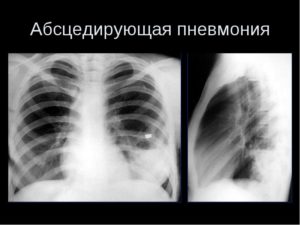

Лечение гнойной (абсцедирующей, септической) пневмонии

Гнойная пневмония — это не болезнь сама по себе, а осложнение первичной пневмонии. Сам процесс характеризуется ограниченными гнойно-деструктивными изменениями легочной ткани, т.е. образованием абсцесса. При неблагоприятном течении может перерасти в септическую пневмонию. В МКБ-10 гнойная пневмония не выделяется как отдельное заболевание, но может быть классифицирована как «пневмония без определенного возбудителя» (J18). Этиология абсцедирующего воспаления легких …